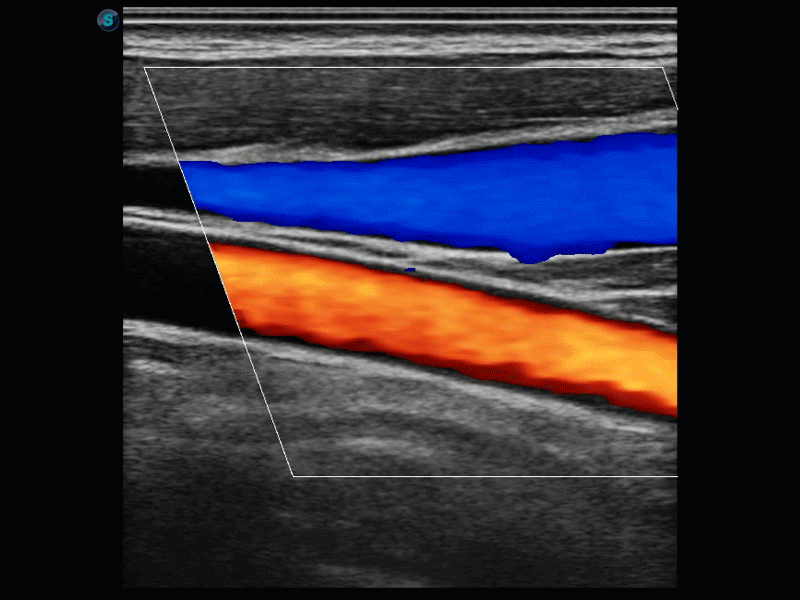

開立醫(yī)療通過不斷的技術(shù)創(chuàng)新,為大眾的生命健康提供持續(xù)關(guān)愛。P12 Plus采用全新一代超聲成像平臺(tái),新平臺(tái)旨在將真實(shí)還原組織解剖結(jié)構(gòu)作為首要目標(biāo)。平臺(tái)采用全新集成化硬件模塊,搭載新一代芯片,系統(tǒng)性能得到大幅提升,為您的診斷提供了豐富的臨床信息。優(yōu)異的圖像表現(xiàn),豐富的探頭配置,全面的應(yīng)用功能,為您日常診斷提供了可靠的助手。

彩色多普勒超聲診斷系統(tǒng)